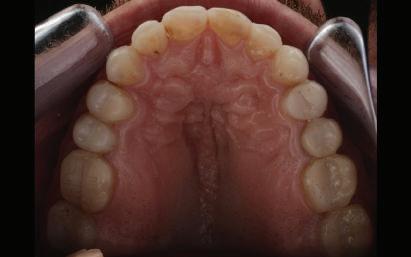

Dental Tribune Bulgarian Edition / октомври 2022 г.16 клиничен случай с алайнери Г орният латерален ре зец е вторият найчесто вродено липсващ зъб.1,2 Поради разполо жението му във видимата зона на усмивката лечение то на подобни случаи нала га мултидисциплинарен под ход, целящ отличен функцио нален и естетичен резултат. Налице са няколко лечебни мо далности, свързани с различ но разпределение на място то: първият вариант е орто донтско отваряне на място и възстановяване на липсва щия зъб с конструкция, под държана от съседните зъби3 или от имплант4, докато при втория подход разстоянията се затварят и премоларът заема мястото на канина.5 Изборът на лечебен подход трябва да бъде направен съв местно от зъболекар и паци ент въз основа на очакванията на последния и предвиди мостта на лечението. Множе ство фактори влияят върху това решение, като напри мер типа малоклузия, размера, формата и цвета на кучеш ките зъби6, оклузалните вза имоотношения (овърджет и овърбайт), лицевия профил, дължината на зъбната дъга и несъответствията в разме ра на зъбите.7 В настоящата публикация се разглежда случаят на жена в зряла възраст с вродена лип са на горен ляв латерален резец. Бяха приложени про зрачни алайнери за отваряне на място за единичен им плант и бяха постигна ти функционална оклузия и отлична естетика. ПРЕДСТАВЯНЕ НА СЛУЧАЯ Диагноза Пациентката бе на 32 годи ни, когато лечението започна, и първоначалното ѝ състоя ние бе следното (фиг. 1–3): липсващ горен ляв латерален резец; клас II, подклас I малоклузия; отклонение на горната сре динна линия вляво; Доклад на клиничен случай ЛЕЧЕНИЕ С АЛАЙНЕРИ НА ПАЦИЕНТ С АГЕНЕЗИЯ НА ЛАТЕРАЛЕН РЕЗЕЦ Д-р Iro Eleftheriadi и д-р Christodoulos Laspos, Гърция и Кипър Фиг. 1a–h Предоперативни лицеви и интраорални снимки. Фиг. 2a–e Дигитални модели преди началото на лечението. Фиг. 3 Панорамна снимка преди лечението. Фиг. 1a Фиг. 1d Фиг. 1f Фиг. 2a Фиг. 2d Фиг. 2b Фиг. 2e Фиг. 3 Фиг. 2c Фиг. 1b Фиг. 1e Фиг. 1g Фиг. 1h Фиг. 1c

планта бе поставена временна коронка (фиг. 10 и 11), докато бъде изготвена окончателна та. Бе постигнат отличен кра ен резултат. Меките тъка ни около импланта напълно заздравяха, което доприне се за перфектната хармония между бяла и розова естетика (фиг. 12–15).

но